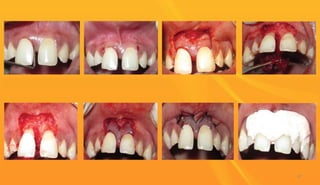

Papilla preservation flap:

 Proposed by Takei et al (1985) later, Cortellini et al (1995,1999) described modifications of

flap design to be used in combination with regenerative procedures.

 For esthetic reasons, the papilla preservation technique is often utilized in the surgical

treatment of anterior tooth regions.

Two types :

 Modified papilla preservation (Cortellini et al, 1995)

 Simplified papilla preservation( Cortellini et al,1999)

A] An intrasulcular incision is made along the lingual/palatal aspect of the teeth with a

semi-lunar incision made across each interdental area.

B] A curette or interproximal knife is used to carefully free the interdental papilla from the

underlying hard tissue.

C-D]The detached interdental tissue is pushed through the embrasure with a blunt

instrument to be included in the facial flap.

E]The flap is replaced and sutures are placed on the palatal aspect of the interdental areas.